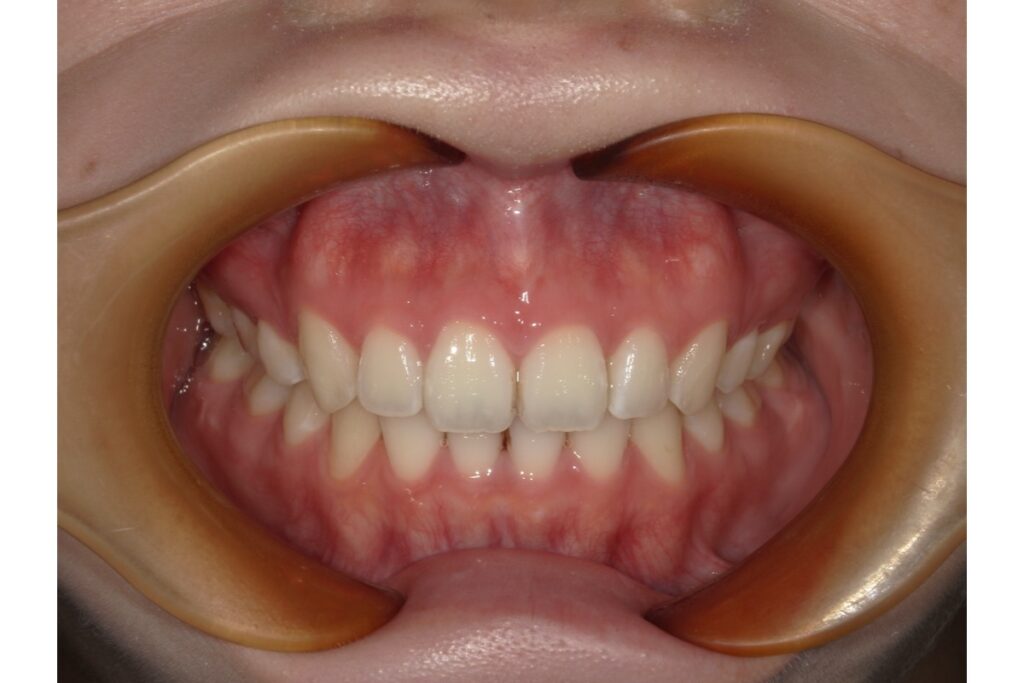

治療終了時の歯並び写真がこちらです↑

治療期間は、約1年半。その期間中に2回マウスピース作り直しをしています!

治療前後の写真を見比べると、前歯の引っ込み具合がよく分かります。

歯を抜いて治療を行っているので、横から見たときの変化がとても分かりやすいかと思います。歯だけではなく、横顔も口元がスッキリしますよ。